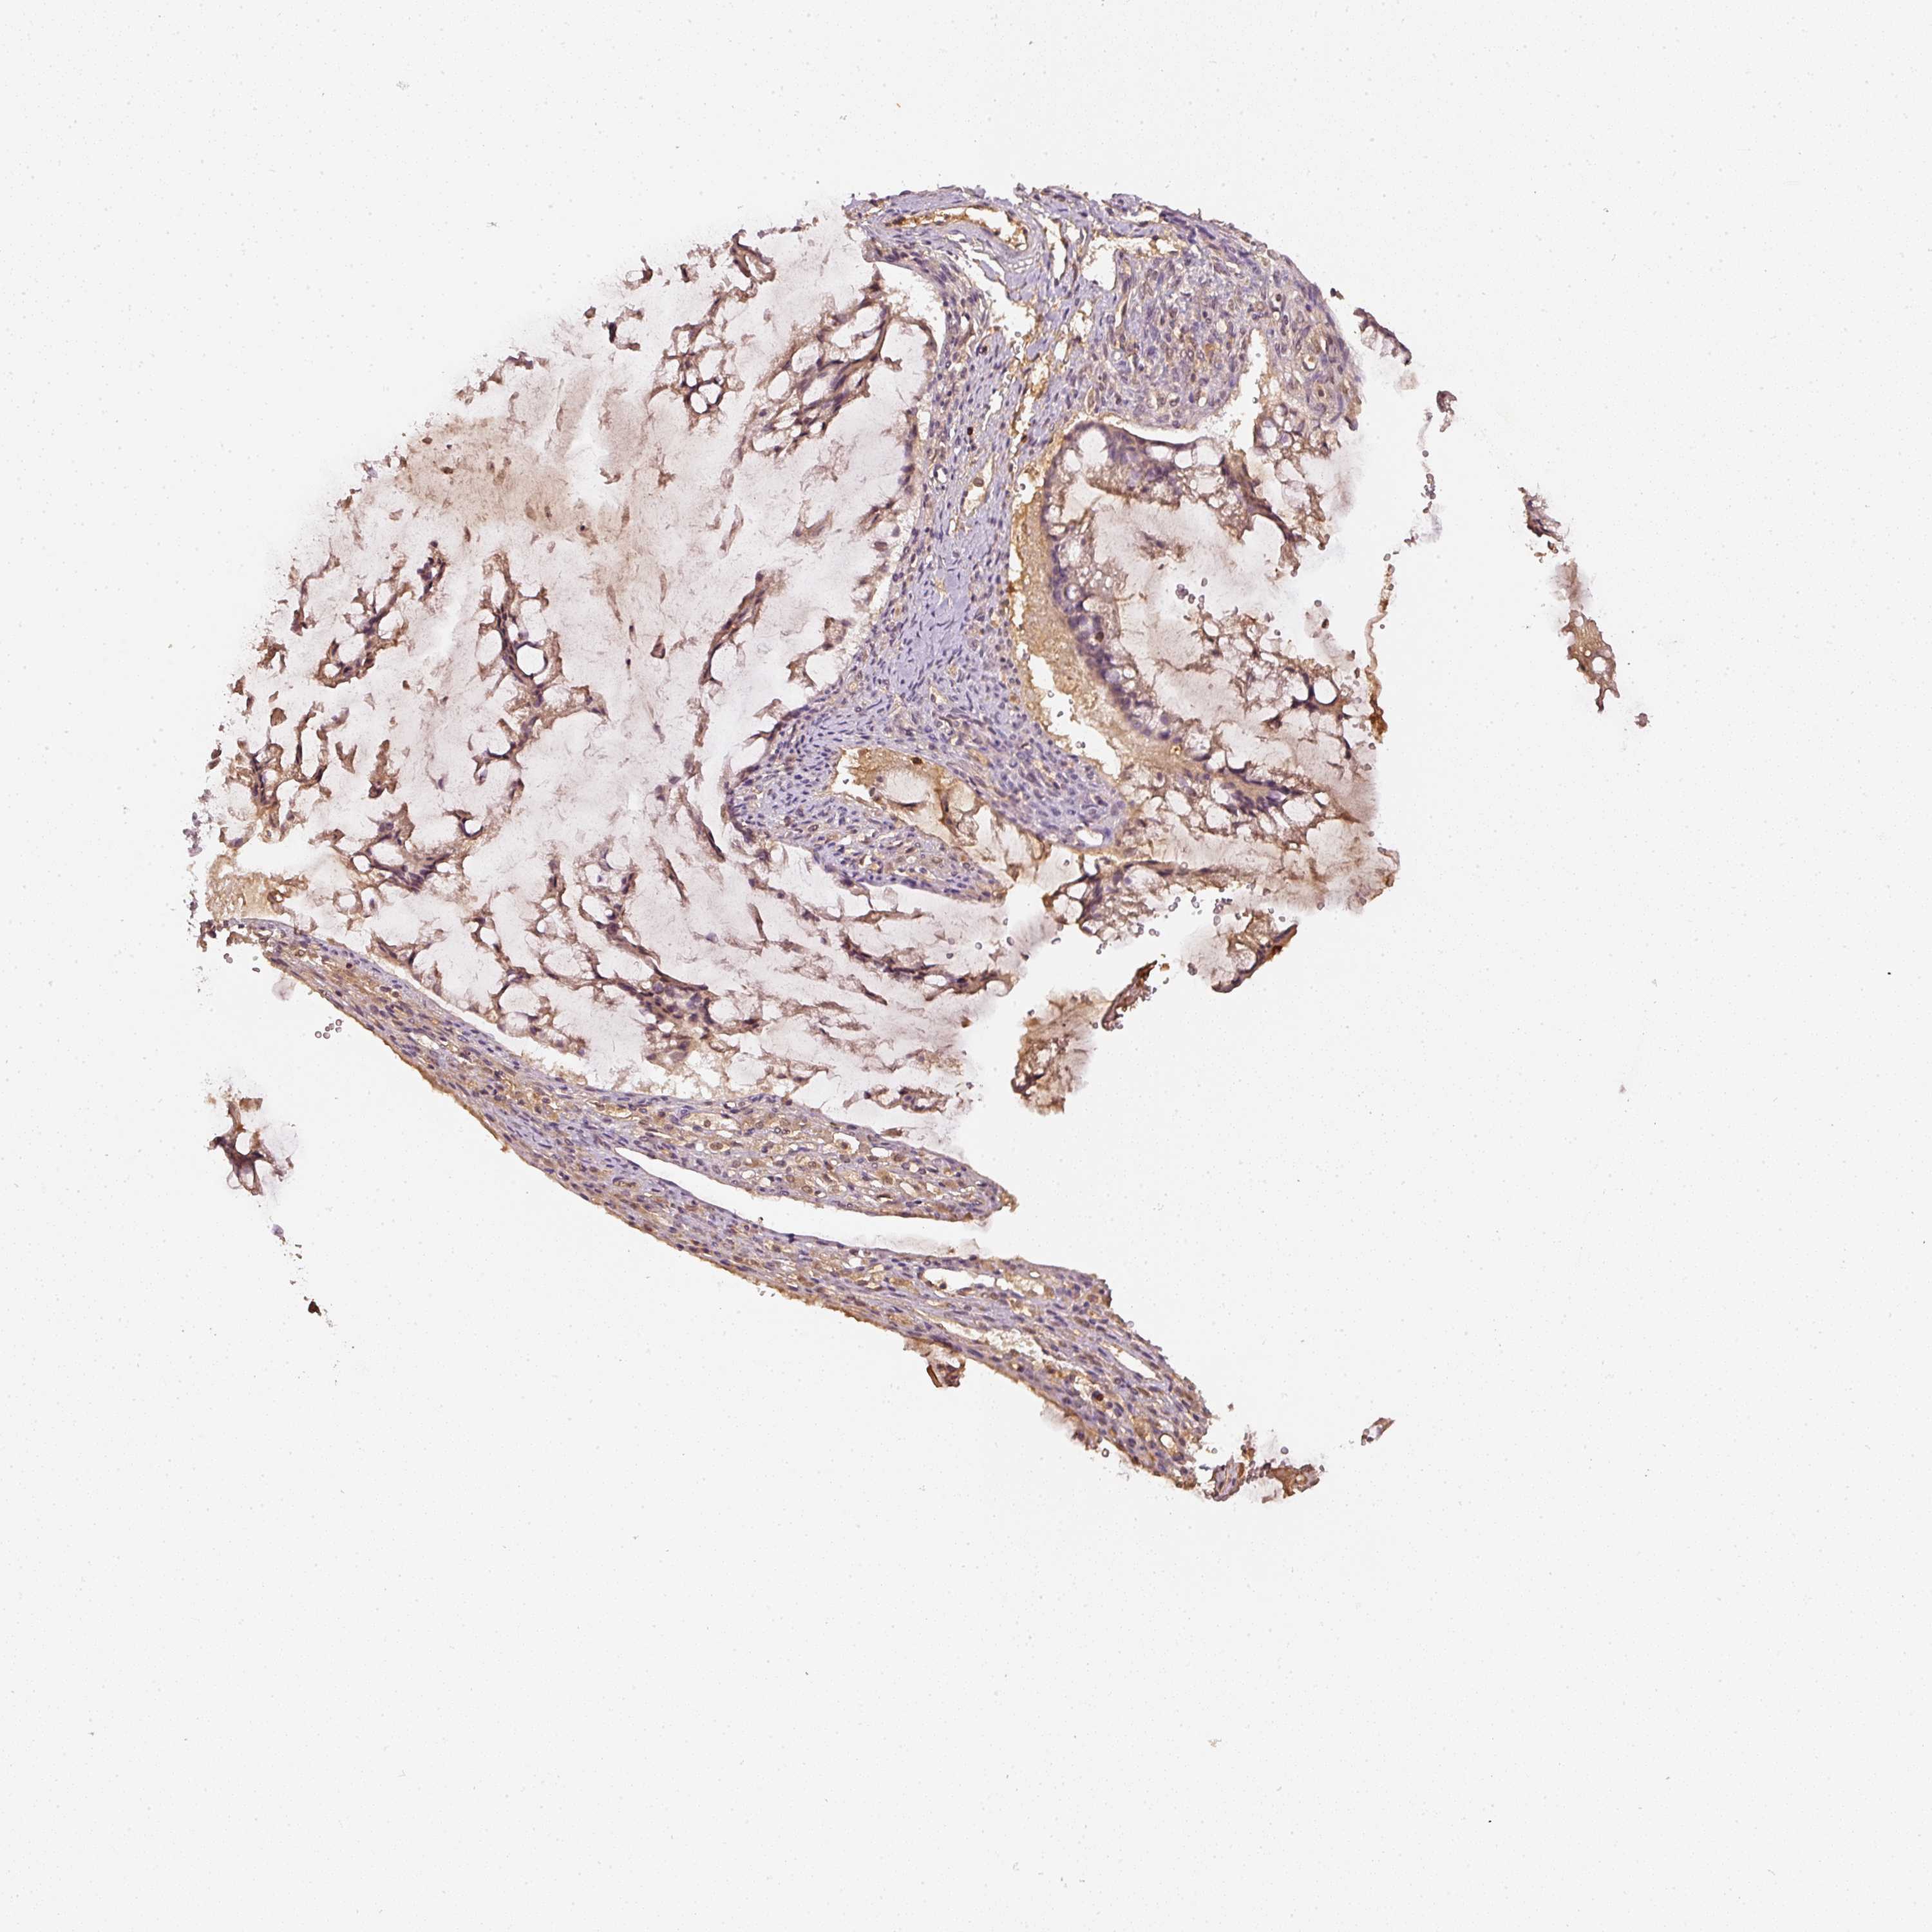

OVARIAN CANCER - Protein expressioni

A mouse-over function shows sample information and annotation data. Click on an image to view it in a full screen mode. Samples can be filtered based on level of antibody staining by selecting one or several of the following categories: high, medium, low and not detected. The assay and annotation is described here.

Note that samples used for immunohistochemistry by the Human Protein Atlas do not correspond to samples in the TCGA dataset.

Antibody stainingi

Antibody staining in the annotated cell types in the current human tissue is reported as not detected, low, medium, or high, based on conventional immunohistochemistry profiling in selected tissues. This score is based on the combination of the staining intensity and fraction of stained cells.

Each image is clickable and will lead to virtual microscopy that enables deeper exploration of all samples and also displays staining intensity scores, fraction scores and subcellular localization as well as patient and tissue information for each sample.

Antibody HPA018849

Antibody HPA019536

Antibody CAB033987

Staining

High

Medium

Low

Not detected

Cystadenocarcinoma, serous, NOS

Carcinoma, endometroid

Cystadenocarcinoma, mucinous, NOS

Carcinoma, NOS